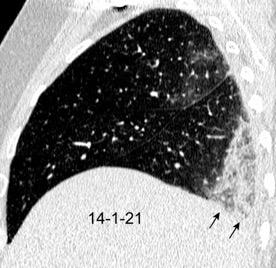

25. ELEVACIÓN UNILATERAL. TEP

Tromboembolismo pulmonar Diafragma elevado 20%